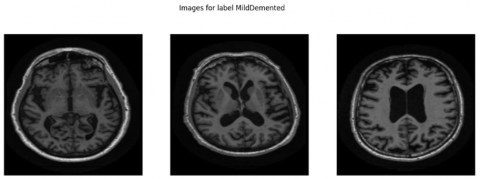

The structural parameters of this dataset show mild bias since it contains 1,216 NonDemented scans while MildDemented scans reach 1,792 images and VeryDemented scans total 706 images. The research data shows good clinical accuracy because healthcare professionals routinely examine more patients with MildDemented conditions. This visual representation in Figure 2 shows MRI cutting planes from each class to represent their structural and intensity differences. The anatomical differences between samples in cognitive processing centers become noticeable in these examples which supports accurate model functioning during training and inference. The varied content of this database enables deep learning models to become effective while they demonstrate multispectral capabilities for AD detection at an early stage.

Figure 2. Sample MRI images from different classes

A proper Exploratory Data Analysis (EDA) was performed in advance to uncover the structural features alongside visual elements and distribution imbalances throughout the dataset. The underlying database consists of 3,714 T1-weighted brain MRI images containing clinical labels of NonDemented, MildDemented and VeryDemented cognitive stage classifications. The three stages of AD organize into separate categories which the labels represent. The main goal of Exploratory Data Analysis included two objectives: first displaying representative images from each class category as shown in Figure 2 and second applying analysis techniques to examine statistical properties which would guide further preprocessing steps and model development.

EDA included qualitative anatomical examinations in several classes as a supplement to histogram analysis. The charting of typical sections images revealed distinct differences in brain structures, particularly at the medial temporal lobe and ventricular areas, which are associated with AD progression. The investigation confirmed that spatial relationships and image textures must be consistently maintained during preprocessing techniques. The team used suitable resizing processes to create standardized images with 224 × 224 pixel dimensions in RGB format, rather than using harsh compression techniques. To suit the needs of pre-trained convolutional networks like VGG16 and MobileNet, which prefer RGB inputs, MRI pictures need to be transformed into three RGB channels.